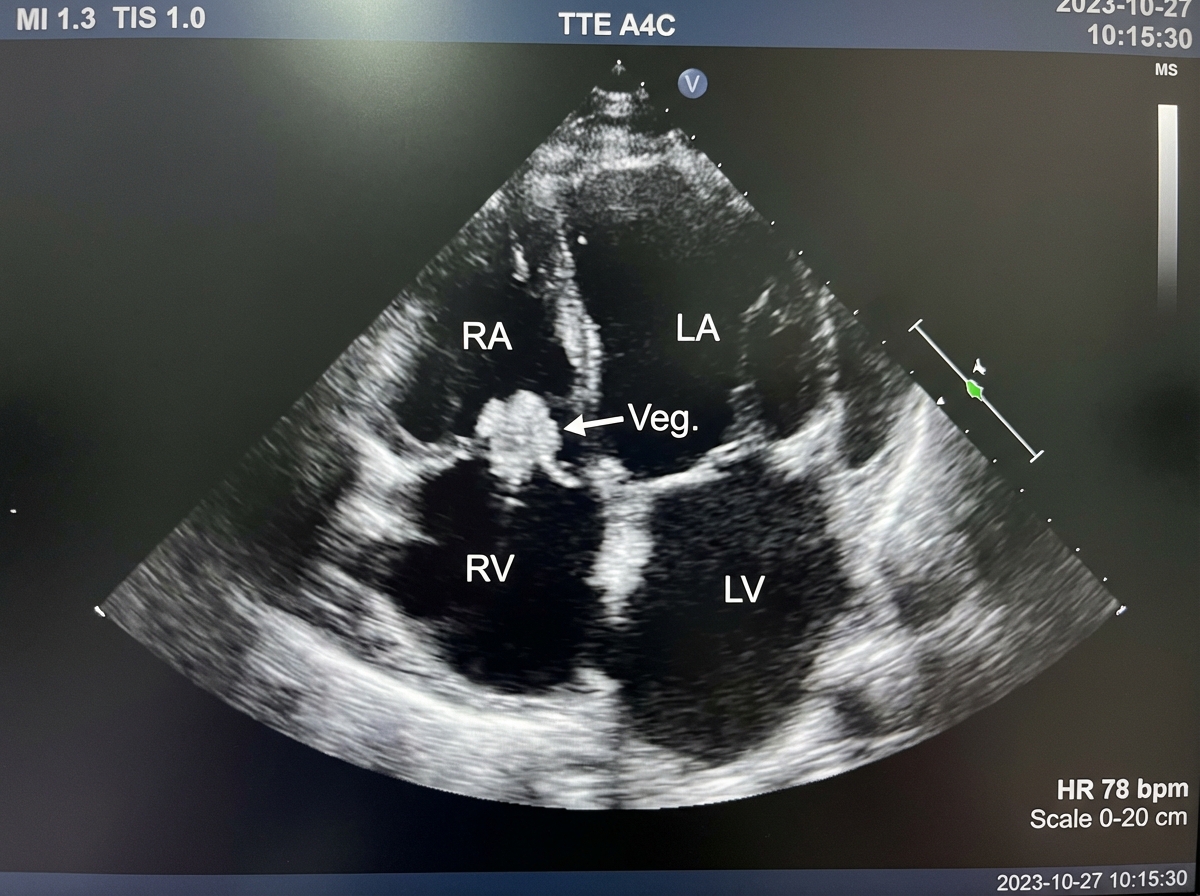

A 27-year-old man from Southern California presents with progressive chest pain, non-productive cough, and shortness of breath for the past 24 hours. He denies any similar symptoms in the past. He denies any family history of cardiac disease, recent travel, or exposure to sick contacts. His temperature is 38.5°C (101.3°F), pulse is 105/min, blood pressure is 108/78 mm Hg, and the respiratory rate is 32/min. On physical examination, patient is cachectic and ill-appearing. Bilateral pleural friction rubs are present on pulmonary auscultation. Antecubital track marks are noted bilaterally. An echocardiogram is performed and results are shown below. Which of the following is the most likely diagnosis in this patient?